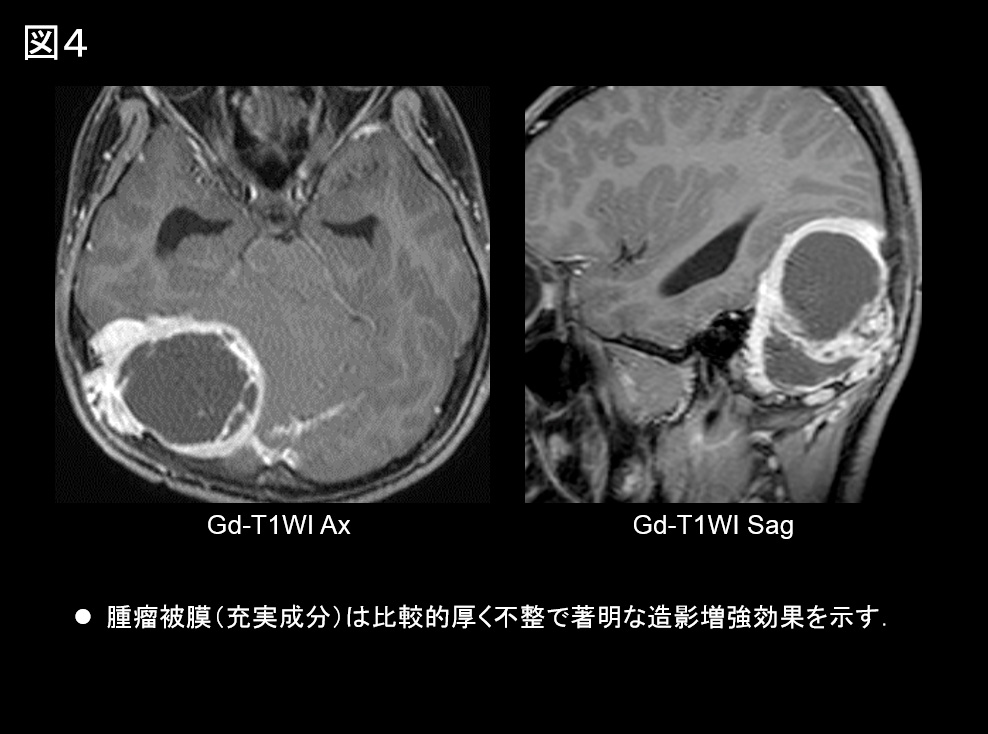

• 腫瘤被膜(充実成分)は比較的厚く不整で著明な造影増強効果を示す(図4)